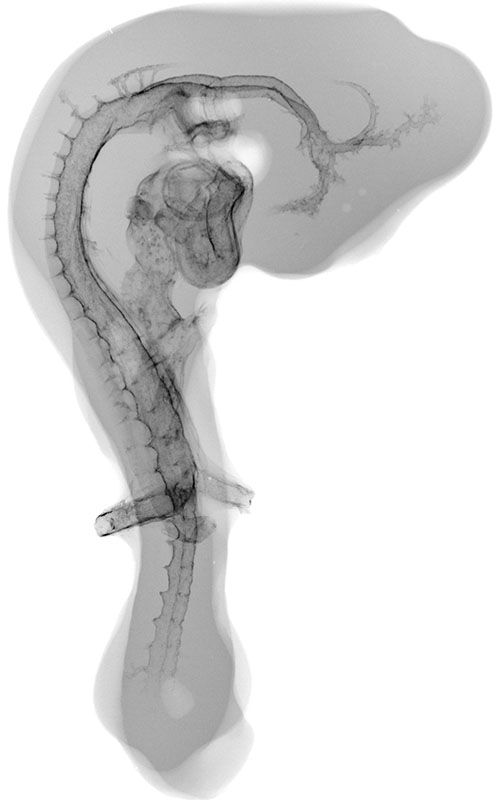

The Chick Embryo Microangiography website is a collection of micrographs depicting the vasculature of chick embryo development from day 2.5 to day 9. The chick typically hatches at day 21. Days 2.5 to 9, as represented in this collection, correspond to Hamburger-Hamilton (HH) stages 16 to 35. Hatching typically occurs at HH stage 46. The collection of images is intended to serve students, researchers, and the general public interested in viewing, studying and teaching animal development.

Composite Image of numerous chick embryo x-ray micrographs